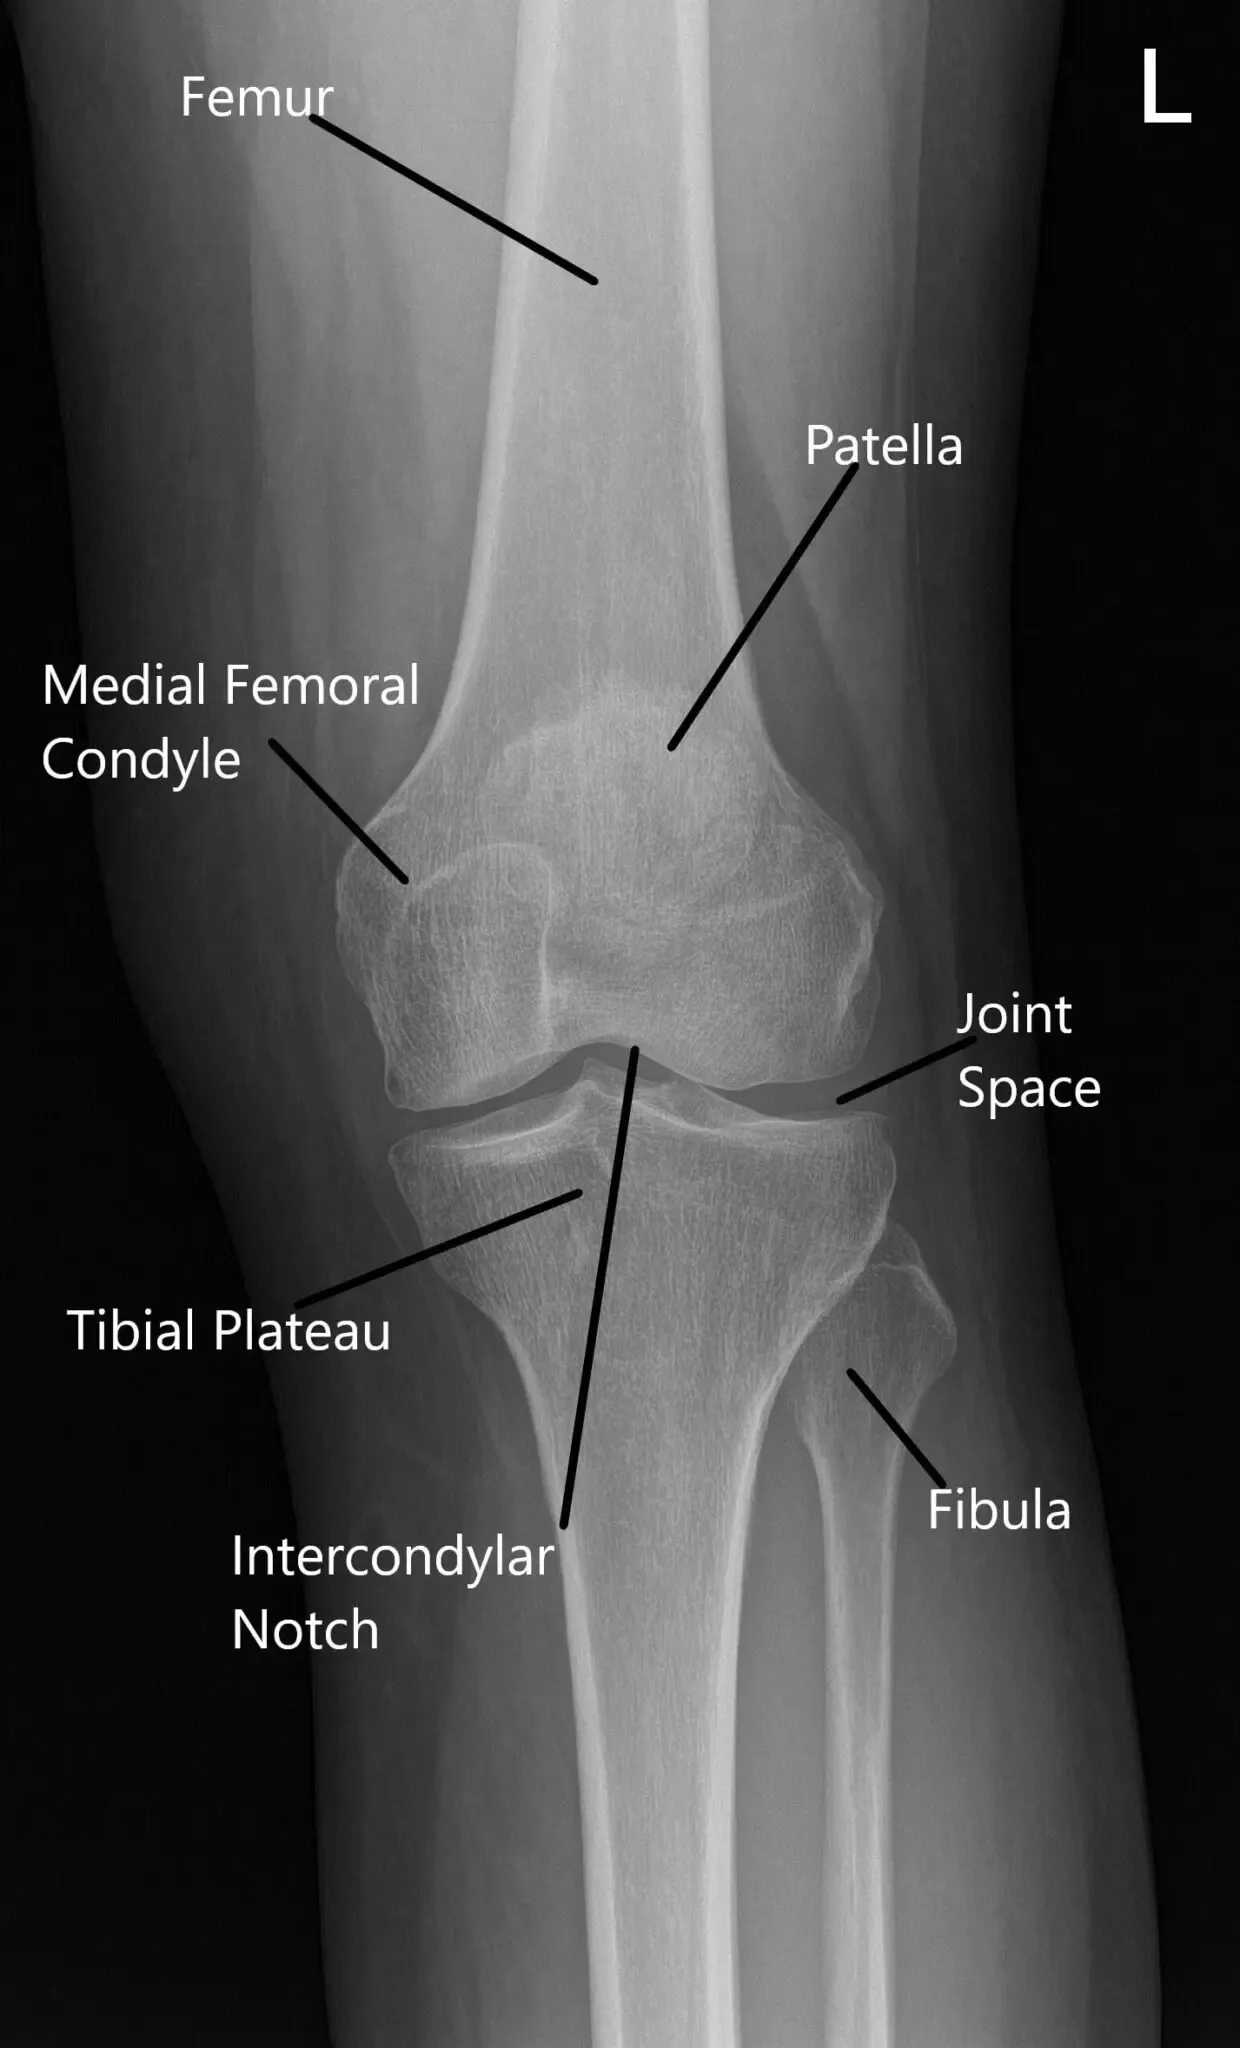

Radiografía de la rodilla izquierda en la vista de la rodilla AP y vista del horizonte de la rótula.